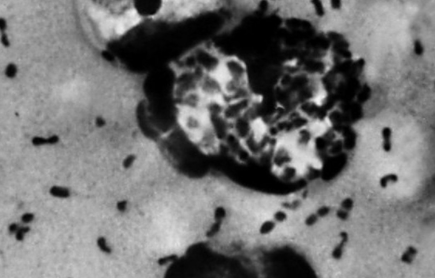

림프절형 페스티(선페스트)는 페스트 균 보유한 벼룩에 의한 흡혈되거나 감염된 동물(사망 개체 포함)의 접촉에 의해 상처나 점막을 통해 체내에 균이 들어옵니다. 페스트 균은 감염 부위의 림프절로 향해 림프절은 균의 증식이 일어나 림프절 조직의 괴사, 농양 형성이 일어나면서 통증과 압통을 오게됩니다.

보통 3 ~ 7 일의 잠복기 후, 림프절 종창과 더불어 발열, 두통, 오한, 쇠약감, 관절통 등 전신 흑사병 증상이 나타납니다. 특히 페스트 균이 침입 부위에서 증식 한 경우 화농성 궤양 및 출혈성 염증이 나타나는 경우도 있습니다. 이번에 발생한 3세 어린이의 중국 흑사병 증상은 이와 비슷했을것으로 추측됩니다.